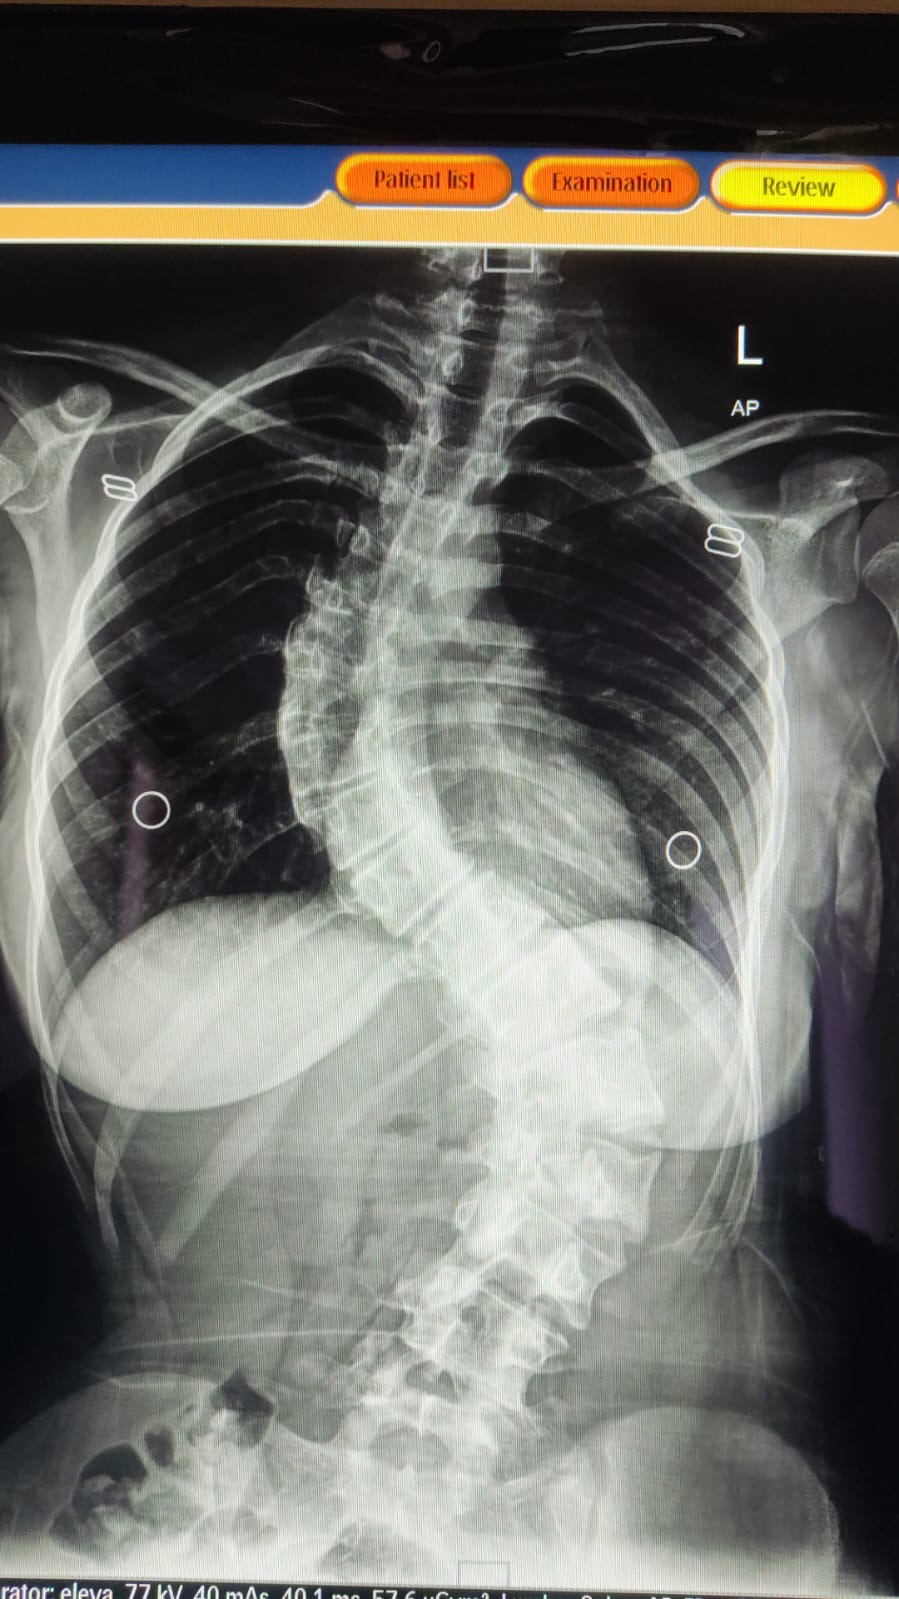

بتوجيهات معالي وزير الصحة إبراهيم البدور، ومتابعة مدير مستشفيات البشير الدكتور الإنسان علي العبدالات، نجح النِّطاسي المبدع الدكتور جاسر الزبيدي في تنفيذ عملية جراحية دقيقة ومعقّدة لإصلاح تشوّه في العمود الفقري لطفلة كانت تعاني من حالة صحية معقّدة.

وجاءت العملية الجراحية بعد تقييم طبي شامل ودقيق للحالة، حيث استخدم الفريق الجراحي أحدث التقنيات المتخصصة في جراحات العمود الفقري، ما أسهم في تصحيح التشوّه وتحسين الاستقرار الوظيفي، وسط متابعة حثيثة لمراحل ما قبل وما بعد الجراحة.

حيث كانت الطفلة تعاني منذ سنوات من تشوّه خلقي في العمود الفقري، الأمر الذي انعكس سلبًا على قدرتها على ممارسة حياتها اليومية بشكل طبيعي، وتسبب لها بآلام وتحديات صحية مستمرة، إلى أن تكللت الجهود الطبية بإجراء هذه العملية الجراحية الدقيقة التي أعادت لها الأمل بتحسّن نوعية حياتها.